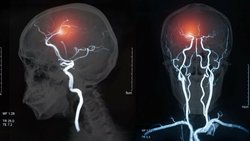

Görüntüleme Çalışmaları

Acil beyin görüntüleme, mimikleri (başka bir hastalığın semptomlarını sergileyen) dışlamak ve potansiyel olarak iskemik inme tanısını doğrulamak için gereklidir. Kontrastsız BT taraması, belirgin akut inmeli hastaların akut değerlendirmesinde en sık kullanılan nörogörüntüleme şeklidir.

BT taraması negatif olduğunda ancak klinik şüphe yüksek olduğunda menenjit veya subaraknoid kanamayı ekarte etmek için lomber ponksiyon gerekir. NCCT'ye BT anjiyografi ve BT perfüzyonunun eklenmesiyle birlikte multimodal BT görüntüleme, büyük damar tıkanıklıklarını ve kurtarılabilir doku alanlarını belirleme potansiyeline sahiptir.

Manyetik rezonans anjiyografi (MRA), inmenin nörogörüntülemesinde büyük bir ilerleme olmuştur. MRG sadece büyük yapısal detay sağlamakla kalmaz, aynı zamanda erken beyin ödemini de gösterebilir. Ek olarak, MRG'nin akut kafa içi kanamanın saptanması için duyarlı olduğu kanıtlanmıştır. Ancak MRG, acil durumlarda BT taraması kadar mevcut değildir, birçok hastanın MRG görüntülemeye (örneğin kalp pilleri, implantlar) karşı kontrendikasyonları vardır ve MRG taramalarının yorumlanması daha zor olabilir.

Karotis dupleks taraması, inmeli hastaları değerlendirmede en faydalı testlerden biridir. Giderek artan bir şekilde, yalnızca inmenin nedenini tanımlamak için değil, aynı zamanda karotis stenozları varsa hastaları tıbbi tedavi veya karotis müdahalesi için sınıflandırmak için değerlendirmede daha erken gerçekleştirilir.

Dijital substraksiyon anjiyografi, oklüzyonlar, stenozlar, diseksiyonlar ve anevrizmalar dahil olmak üzere vasküler lezyonları göstermek için kesin yöntem olarak kabul edilir.